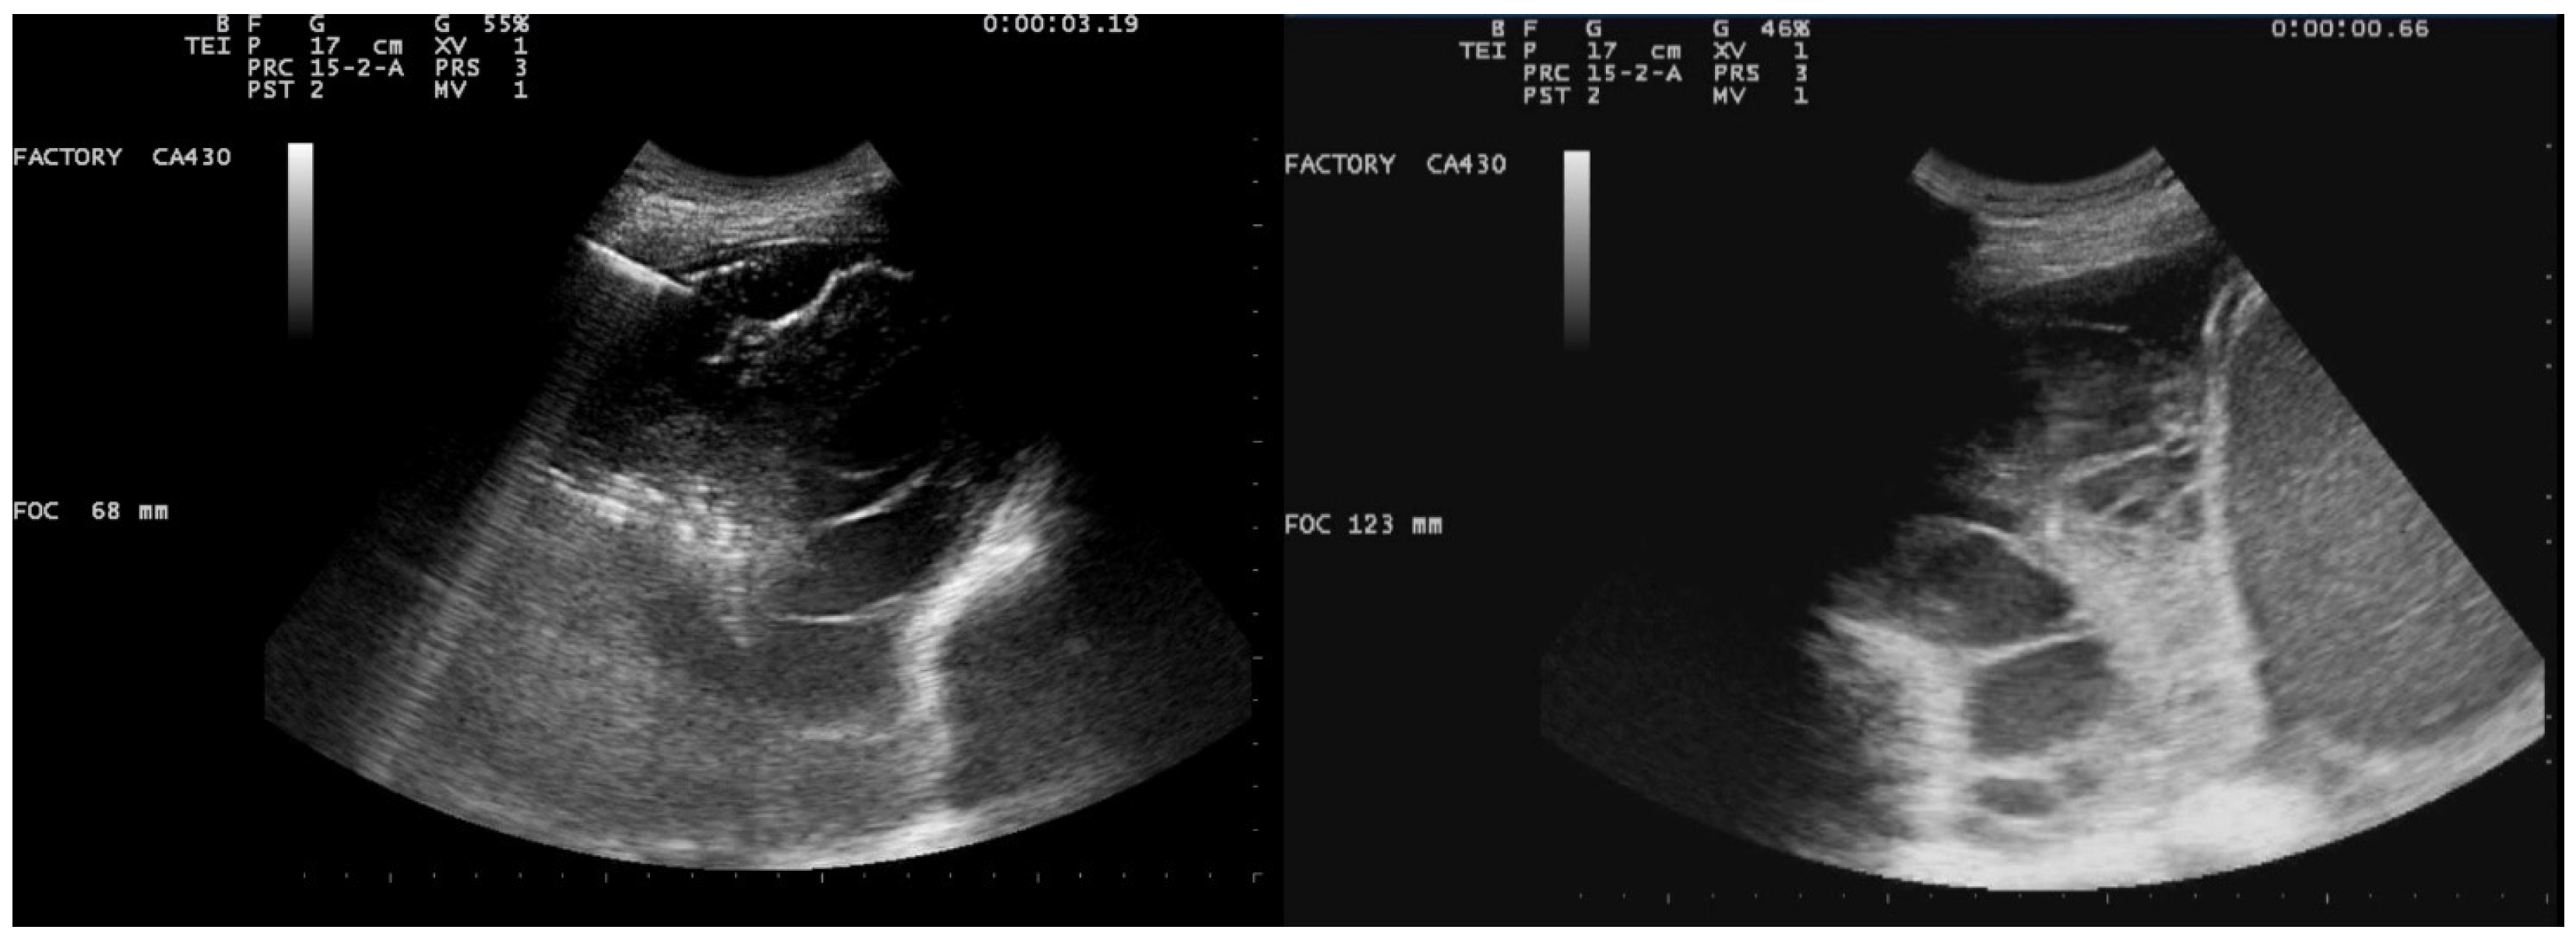

A chest US showed multiloculated PEff with septations of different thicknesses (Figure 9). A 12 Fr chest tube was placed, and 1000 mL of turbid fluid were drained. Samples were collected for microbiological and physicochemical analysis. Irrigation of the pleural cavity with 200,000 IU of urokinase in 50 mL of saline solution was performed under US guidance (Video 1). This was followed by the closure of the chest drain for 3 h, and then it was reopened. Further irrigation with 100,000 IU was performed 24 h later. Empiric antibiotic therapy with 500 mg azithromycin (q24h) for 6 days and 4.5 g piperacillin/tazobactam (q8h) for 2 weeks was administered. A chemical analysis of the pleural fluid revealed exudate. The microbiological study was negative.

Ultrasound observations 48 h after the administration of the first dose of urokinase showed the absence of fibrinous septa and a significant decrease in PEff (Figure 10 and Figure 11).

Figure 9. Chest ultrasound at admission showing multiloculated pleural effusion.

Figure 10. Chest US 48 h after urokinase. Minimum pleural effusion with residual fibrinous material and signs of lung re-expansion.

Figure 11. Chest US 48 h after urokinase. Chest tube in pleural cavity with residual pleural effusion.